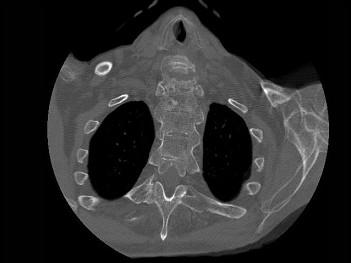

问题 男,92岁,下腰不适伴晨僵半年余,请结合影像学检查,选出最可能的诊断 ( )

选项 A、阻滞椎 B、类风湿关节炎 C、强直性脊柱炎 D、化脓性脊柱炎 E、脊椎退行性变

答案 C